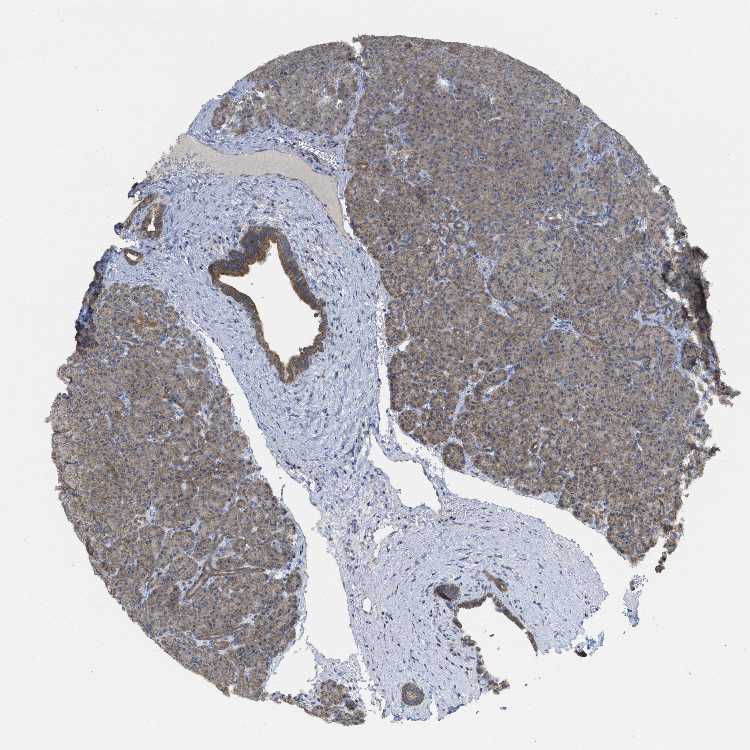

TISSUE PRIMARY DATA PANCREAS Show tissue menu

PANCREAS - Antibody stainingi

Antibody staining in the annotated cell types in the current human tissue is reported as not detected, low, medium, or high, based on conventional immunohistochemistry profiling in selected tissues. This score is based on the combination of the staining intensity and fraction of stained cells.

Each image is clickable and will lead to virtual microscopy that enables deeper exploration of all samples and also displays staining intensity scores, fraction scores and subcellular localization as well as patient and tissue information for each sample.

Antibody HPA018150Antibody HPA026834

Exocrine glandular cells MediumMedium

Pancreatic endocrine cells Not detectedLow